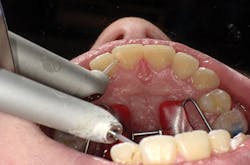

Figure 3

I'll demonstrate this material's versatility with a few cases. First is a large Class III cavity. The patient was extremely apprehensive, so we decided to prepare the cavity using the Lite Touch (AMD Lasers) erbium YAG laser. Very often, as in this case and the next few cases that we will depict, cavity preparation can be performed without anesthetic. In Figure 1, we see the preoperative image of the large Class III cavity on tooth No. 8. Using the Lite Touch laser (figure 2), we were able to excavate the entire cavity in a clean and efficient manner (figure 3). Using a fine diamond, a slight bevel was completed on the enamel at the cavo surface margin. By beveling the enamel, we improve the bond of the adhesive and allow for a seamless blend of the restorative material to the outer tooth structure. In deep restorations such as this, a calcium liner can help minimize sensitivity and act as a buffer between the restoration and pulp. Both Calcimol LC (Voco) and Theracal (Bisco) can be used in this manner. In this case, we decided to use Theracal. Theracal was placed in the deepest area and light-cured for 15 seconds (figure 4). After a 37% phosphoric acid etch of the enamel margin, we applied Futurabond U (Voco) as per the manufacturer's instructions and light-cured for 10 seconds. Admira Fusion shade A2 was placed in three increments and polished. The final restoration exhibits a beautiful luster and a seamless blend from the restoration to the natural tooth (figure 5).